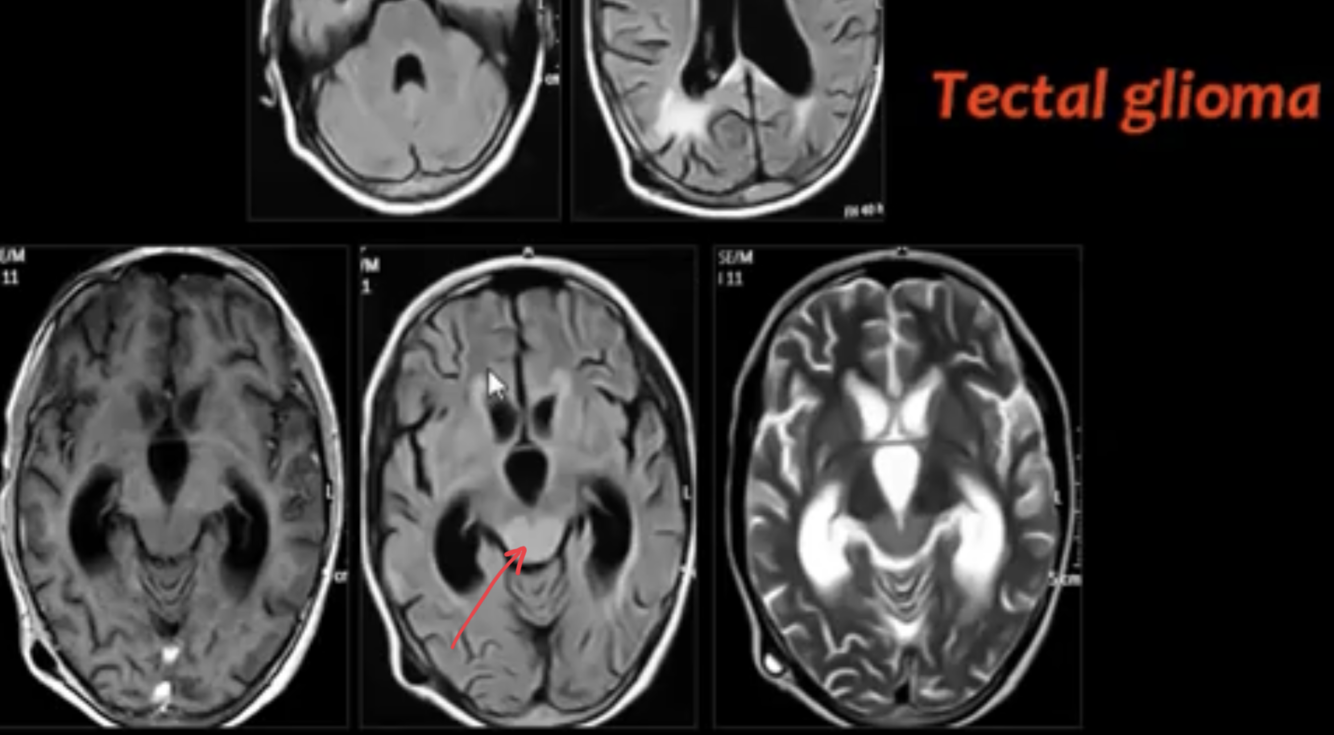

TECTAL GLIOMAS

major points